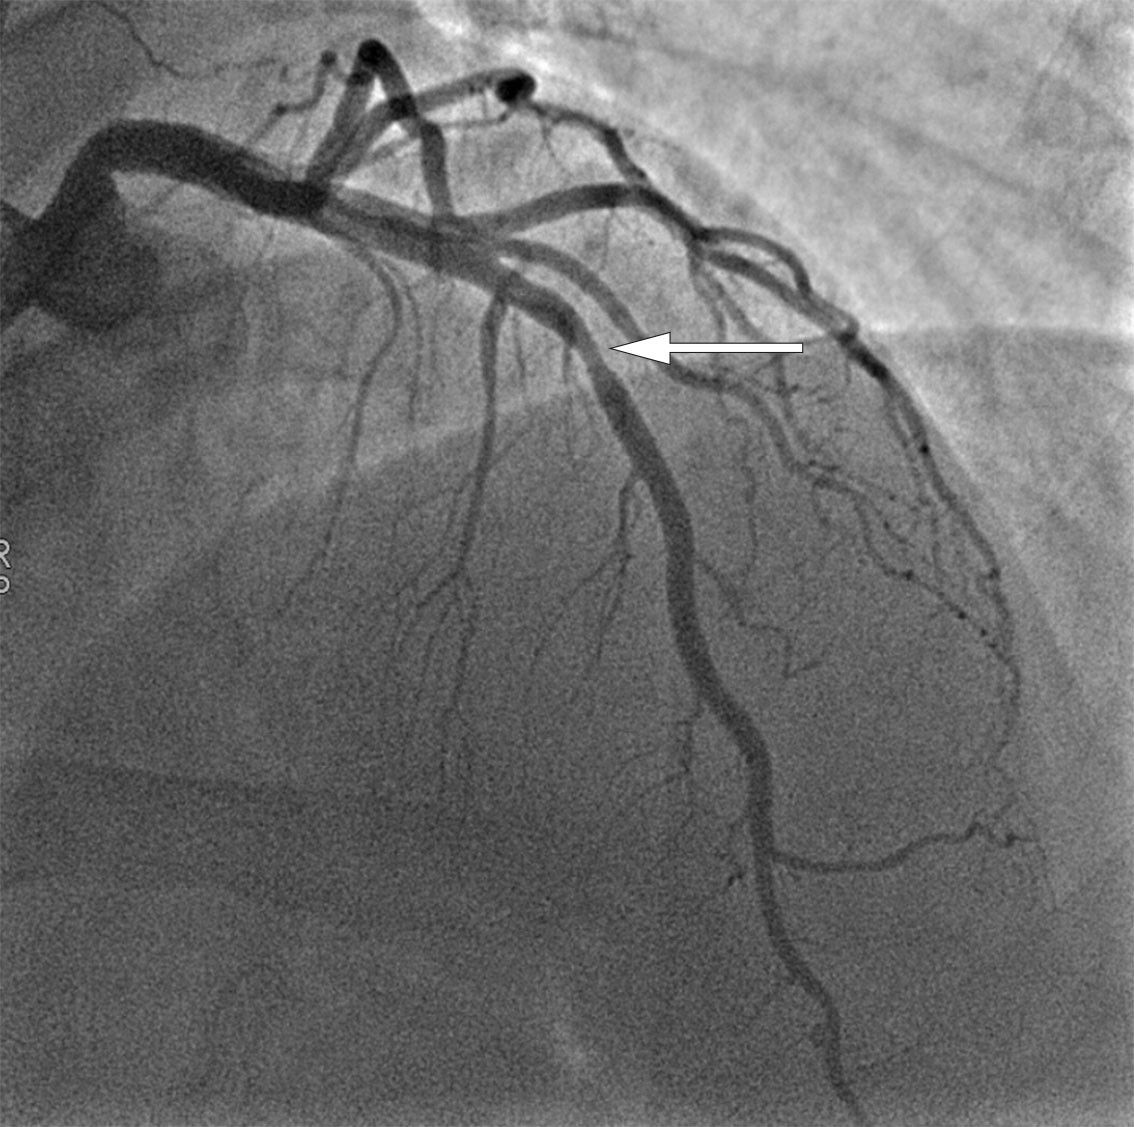

Samme dag som ST-elevasjoner ble dokumentert, ble det utført invasiv koronar angiografi for å utelukke akutt iskemi. Koronar angiografi viste en stenose i den proksimale delen av venstre koronararteries fremre nedadstigende gren (LAD, left anterior descending artery) (figur 3). Det ble gitt 2 mL nitroglyserin intrakoronart to ganger under undersøkelsen, hvor stenosen forble uendret. Stenosen ble mistenkt å være årsak til symptomene (culprit-lesjon), og det ble utført perkutan koronar intervensjon (PCI) med en medikamentfrigjørende stent (Medtronic Resolute Onyx 3,5/15 mm).

Stenting av et koronarkar med vasospasme anbefales bare dersom det samtidig foreligger obstruerende koronarsykdom (6). Hos vår pasient avdekket koronar angiografi en mulig stenose i proksimale del av LAD-arterien. Denne stenosen ble vurdert som såkalt culprit-lesjon, og dermed stentet. Det ble ikke gjort trykkmåling over stenosen eller optisk koherens-tomografi (OCT) for å kartlegge lesjonen nærmere. Ved tvil om hvorvidt en stenose er av hemodynamisk betydning, bør det kartlegges om det foreligger signifikant trykkfall over stenosen. For å vurdere lesjonens stabilitet eller for å avdekke en eventuell plakkruptur kan karet undersøkes ytterligere med OCT eller intravaskulær ultralyd, noe som ikke ble utført hos vår pasient. Retroperspektivt kan man heller ikke utelukke at det hele skyldtes vasospasme i karet.